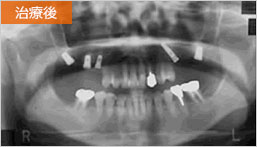

インプラント症例7

45歳 男性- 治療期間 4か月(埋入手術から上部構造装着まで)

- 治療費 ¥1000,000(税別)

右側(Rと書いてあるほう)をご覧ください。骨に入っている部分と骨から出ている部分の長さの比に注目です。骨が少なくてもインプラント可能です。術後6年が経ち順調な経過といえます。